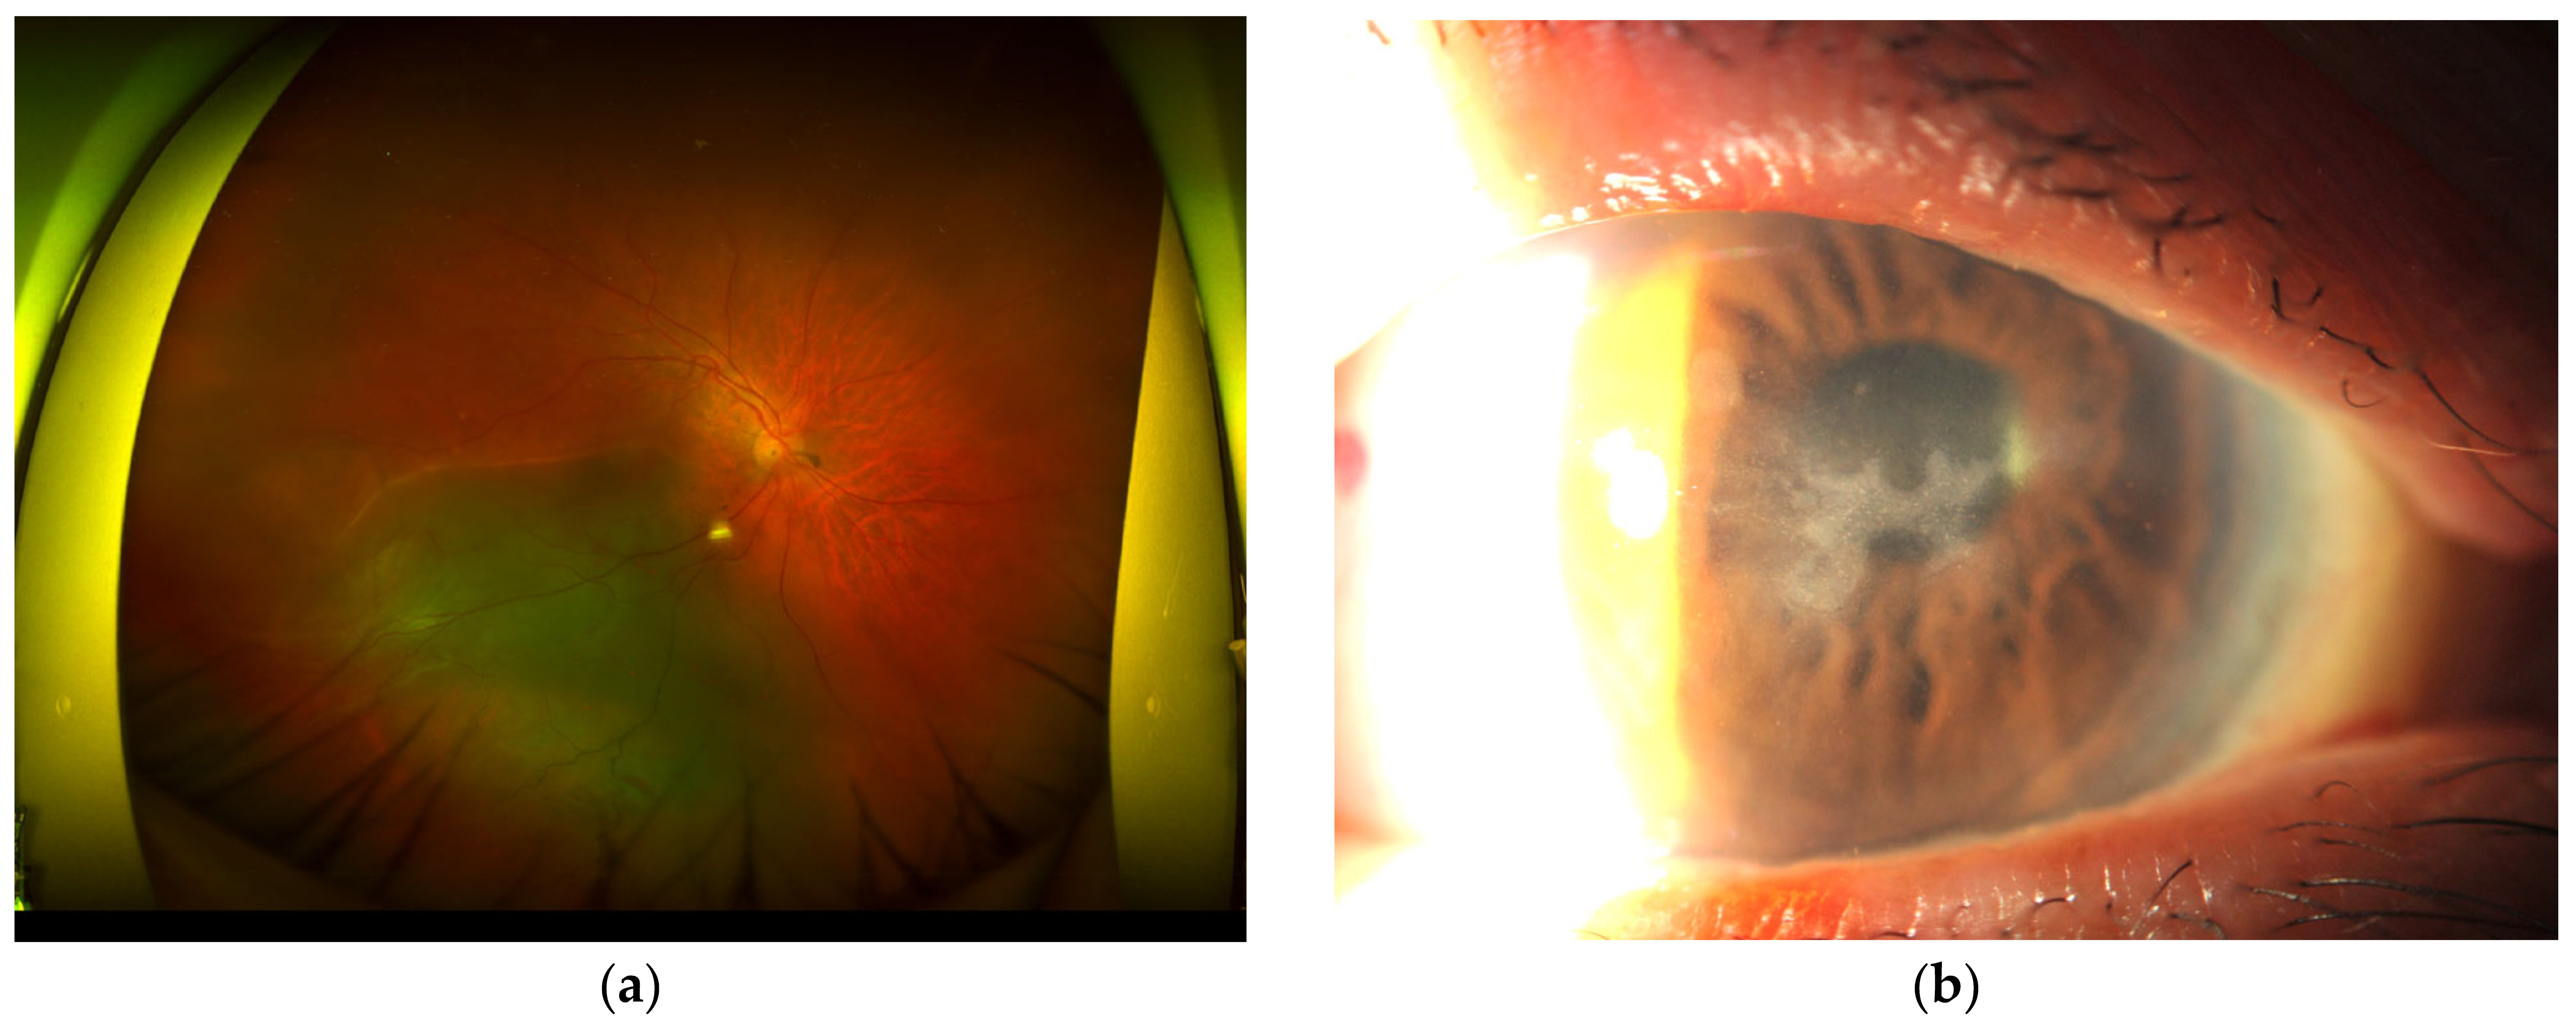

3. Case Presentation 2